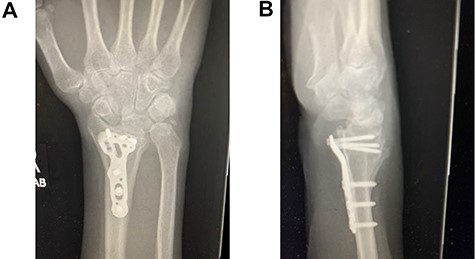

Following appropriate consultation and consent, she underwent total wrist arthroplasty. She reported complete pain relief and an improved range of movement. Ten weeks following surgery the patient presented in the emergency department following a fall. She landed heavily on the dorsiflexed hand and wrist, immediately noticing a change. Imaging confirmed that she had sustained a periprosthetic fracture in the middle finger metacarpal with dorsal displacement of the implant (Fig. 2A and B). Following a trial of non-operative treatment, she underwent revision surgery. The distal metacarpal implant was removed and replaced with a longer implant and the metacarpal fracture defect region was reinforced with autologous bone graft (Fig. 3A and B).

(A and B) PA and lateral radiographs showing a periprosthetic fracture around the metacarpal implant of a Motec wrist replacement.